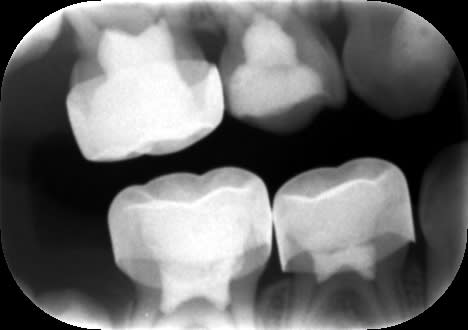

Dans le cas ci-dessous, la 1ère photo est prise après début d’éviction carieuse : sur la 4, on voit déjà la pulpe par transparence. Les tubuli dentinaires d'une dent temporaire sont beaucoup plus larges et nombreux que sur une dent permanente. Ainsi, une carie dentinaire infecte très rapidement la pulpe camérale. Faire une restauration sans pulpotomie dans ce cas aurait probablement abouti à une nécrose à moyen terme.